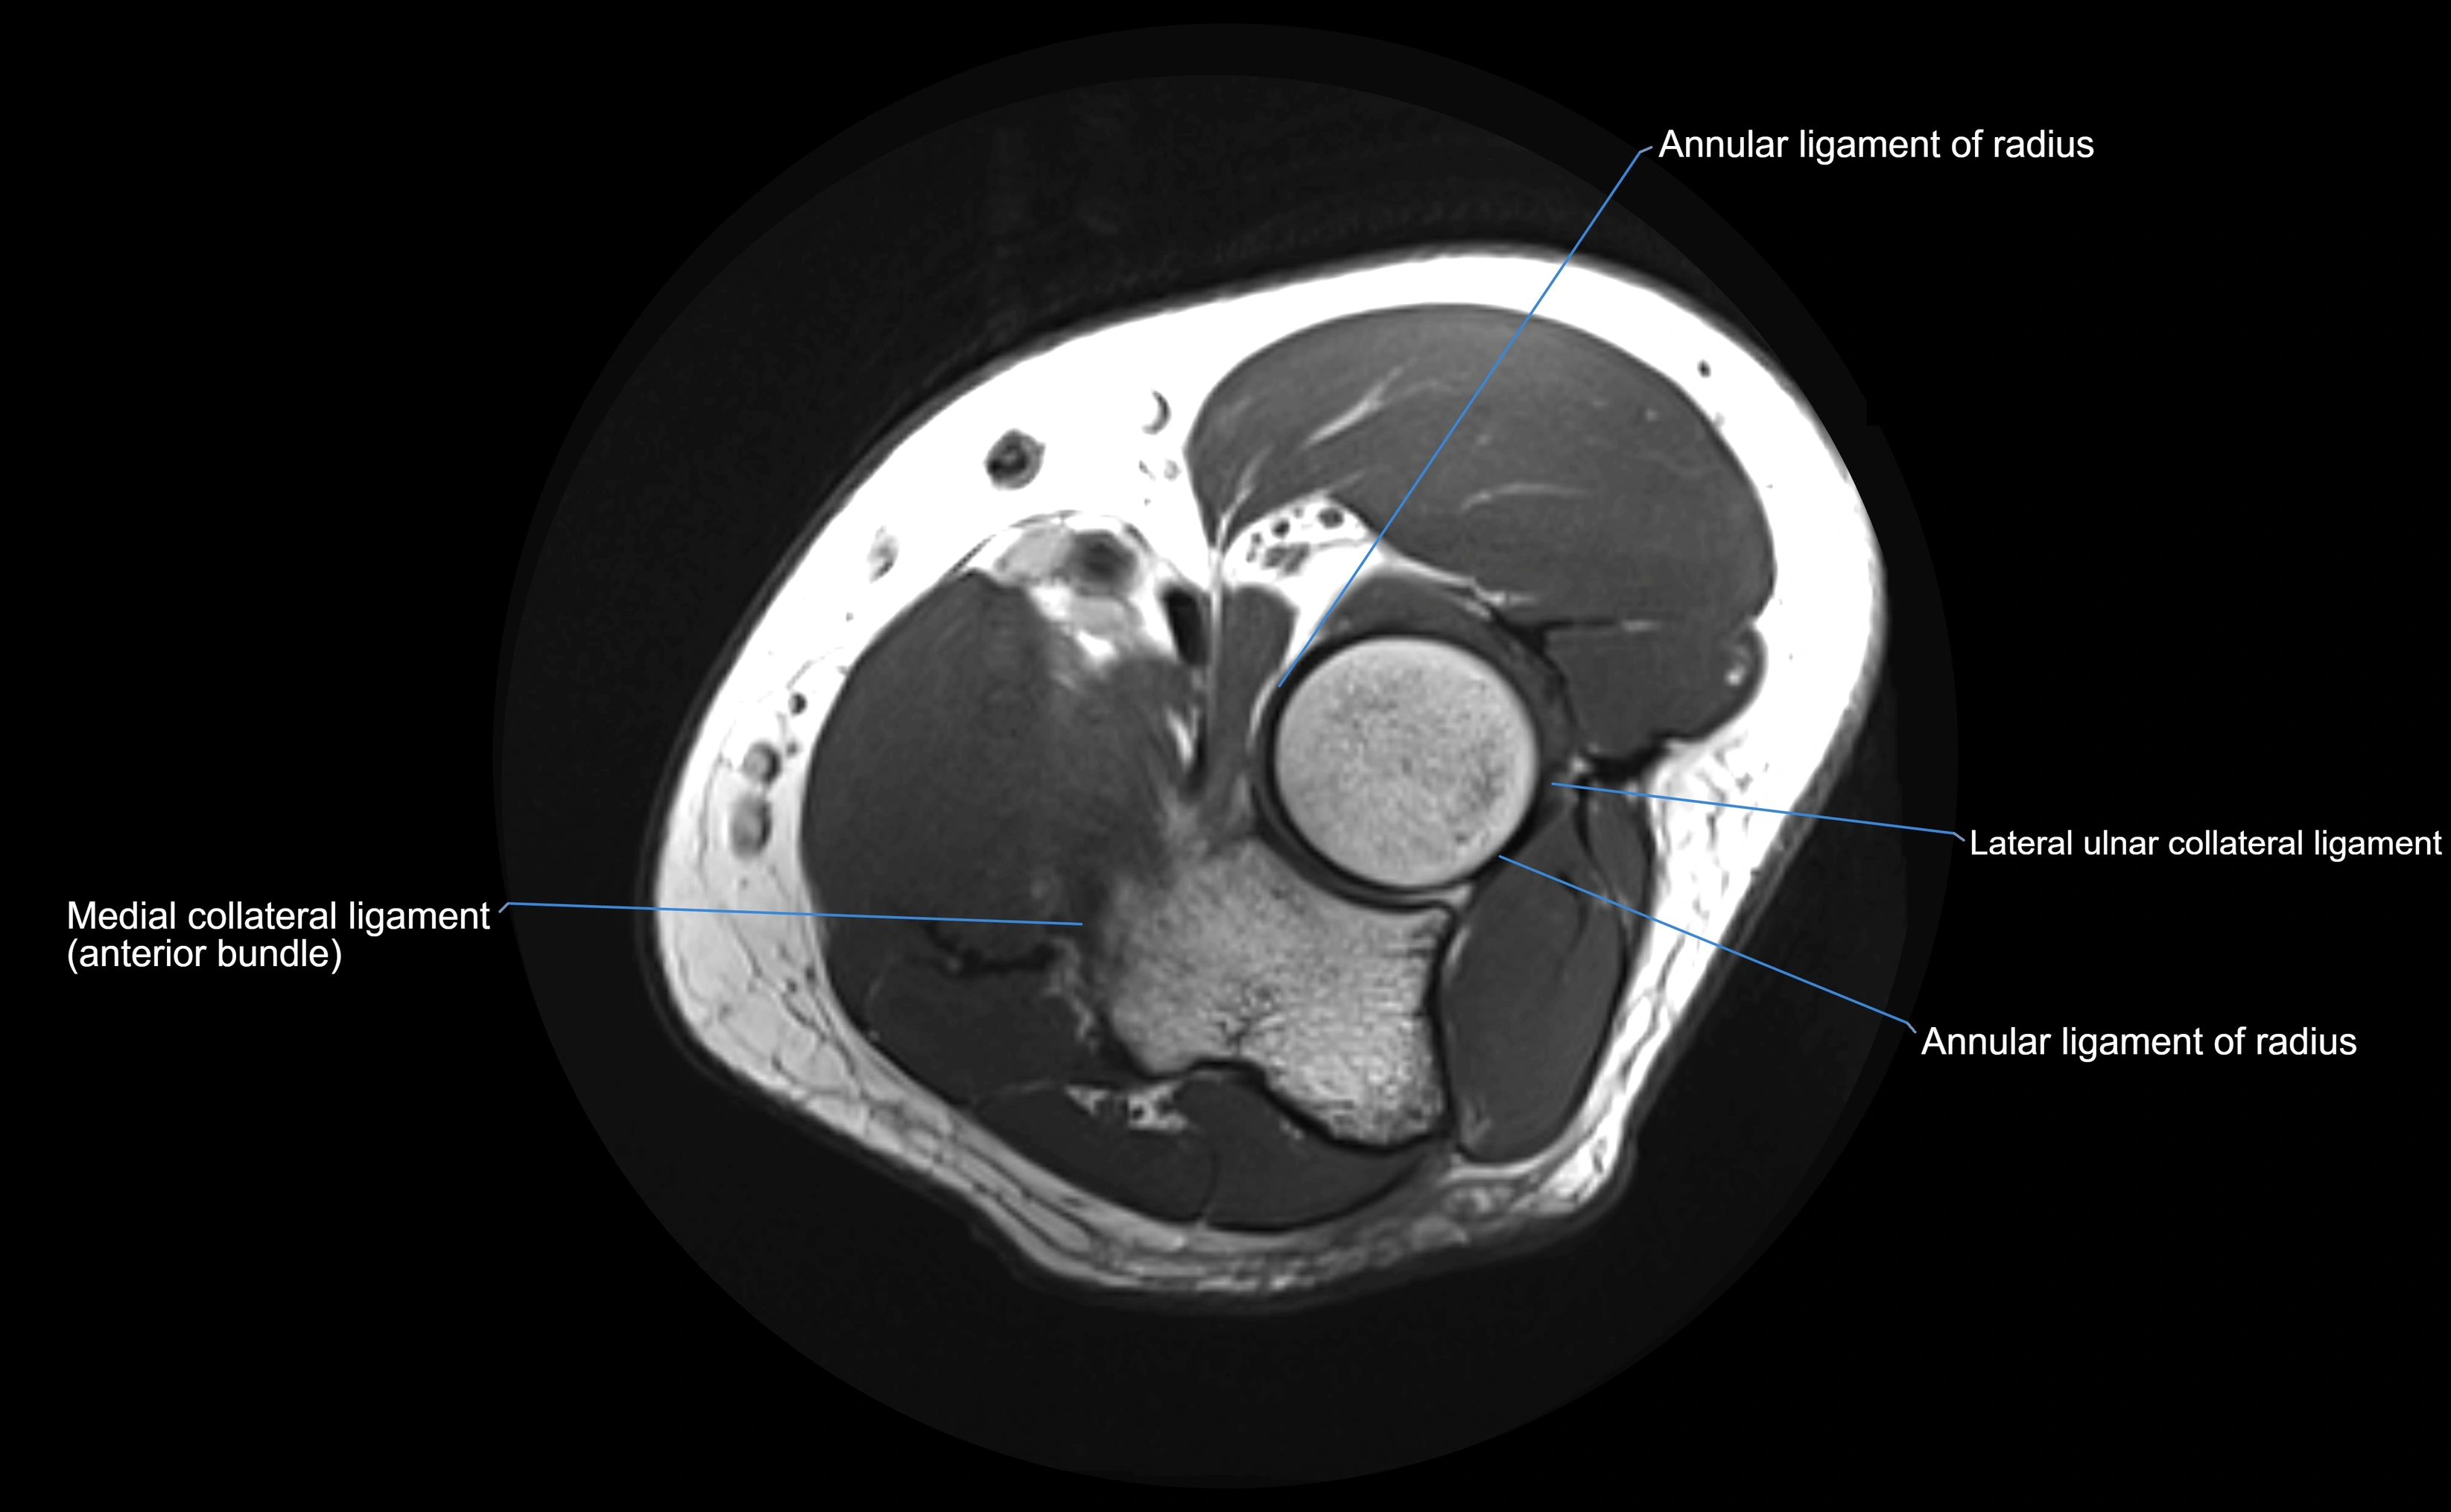

MRI Appearance

T1-weighted images:

• Ligament: low signal intensity (dark), appearing as a continuous band around the radial head.

• Adjacent fat and marrow: bright, creating contrast with the ligament.

• Thickening or disruption indicates injury or fibrosis.

• Joint capsule and synovium seen as thin low-signal lines contiguous with ligament margins.

T2-weighted images:

• Ligament: low signal (dark) with clear delineation from joint fluid.

• Fluid or edema: bright hyperintense, separating or surrounding the ligament in partial tears.

• Complete tear: discontinuity or non-visualization of ligament fibers, often with joint effusion.

STIR:

• Normal ligament: dark band encircling radial head.

• Pathology: bright hyperintense periligamentous signal suggesting edema, sprain, or partial tear.

Proton Density Fat-Saturated (PD FS):

• Normal: dark, well-defined band outlining the radial head.

• Partial tear: irregular or bright hyperintense signal within or adjacent to ligament fibers.

• Joint effusion and reactive synovitis appear bright and are well visualized.

MRI Arthrogram Appearance

• Contrast outlines the proximal radioulnar joint and radial head recess.

• Normal ligament appears as a dark ring surrounding the radial head, containing the injected contrast within the joint cavity.

• Partial tear: contrast extends along the ligament or beneath its fibers.

• Complete tear or subluxation: contrast extravasates around the radial head or ulna, indicating discontinuity.

• Detects capsular defects, instability, or synovial invagination with high sensitivity.